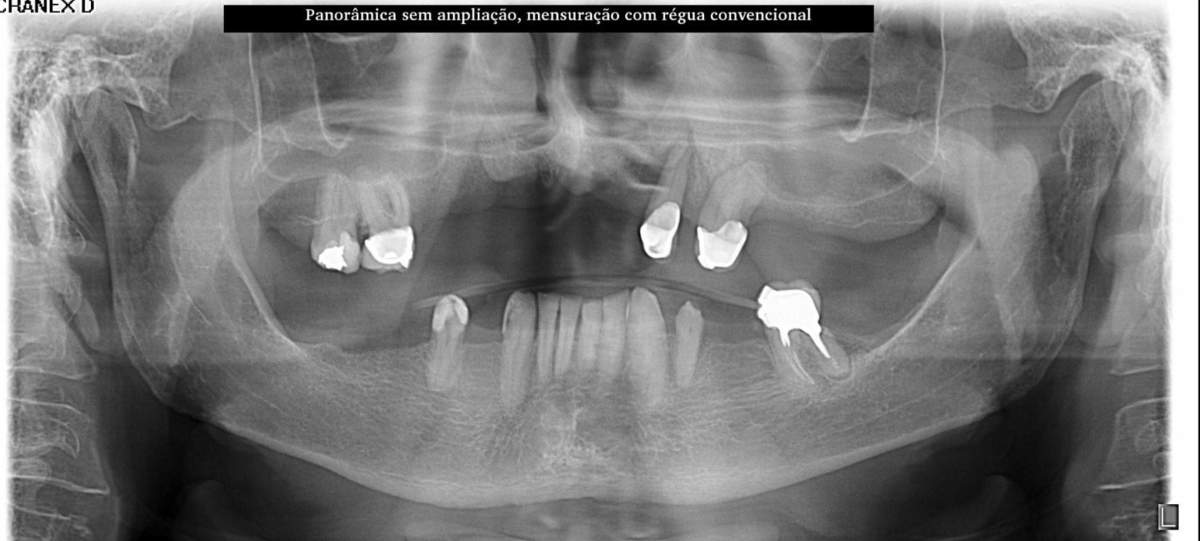

PRÓTESE TOTAL FIXA EM IMPLANTES

R.A.A.